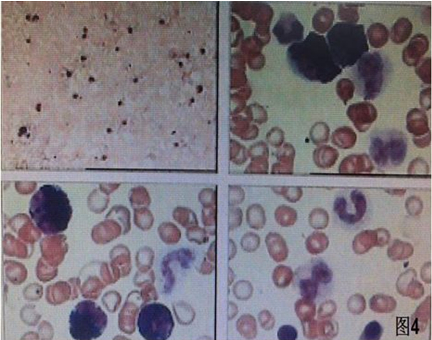

1 资料与方法患者男,30岁,因“腹胀、腹痛6 d,高热1 d”于2017年12月11日由广州南沙区中心医院转诊收入中山大学孙逸仙纪念医院全科医学科。患者本次起病前无明确病因或明显诱因。患者以左上腹轻微胀痛起病,进行性加重。南沙区医院查血常规:白细胞14.27×109/L,血小板50×109/L,中性粒细胞比例74.5%,嗜酸粒细胞1.02×109/L,嗜酸粒细胞比例7.2%。全腹CT+CTA提示:门静脉左右主干及其小分支栓子形成。后在3 d内连续复查血常规,提示血小板进行性下降,由50×109/L相继降至35×109/L、18×109/L;(嗜酸粒细胞计数及比例未能提供),并出现高热(体温39.5℃),因病情危重,遂转诊本院。入院时患者精神疲乏、高热,腹部胀痛难忍,伴有咳嗽。查体:体温38.6℃,心率87次/min,血压102/76 mmHg,指尖血氧饱和度90%~91%。双肺呼吸音粗,双肺均可闻及小水泡音。腹部稍膨隆,叩诊鼓音,左上腹及脐周轻压痛,无反跳痛。听诊肠鸣音减弱,约1~2次/min。当天查血常规示白细胞11.85×109/L,血小板23×109/L,中性粒细胞比例58.1%,嗜酸粒细胞3.5×109/L,嗜酸粒细胞比例29.5%。凝血常规提示:PT 15.9S,PTA 51.1%,PT/R 1.39,Fbg 1.59 g/L,PTINR 1.39,APTT 35.2 s,D-二聚体114.36 mg/L FEU(参考值范围0~0.55 mg/L FEU)。胸部+全腹部CT+CTA示“门静脉主干及左、右支、肠系膜上静脉近端栓子形成;腹主动脉及左侧髂总动脉小附壁血栓;左肺上叶尖后段、左肺上叶下舌段、右肺中叶及双肺下叶炎症;乙状结肠两段节段性管壁增厚,建议排外占位性病变;腹水、盆腔积液,大网膜炎性病变可能性大”。每日复查血常规,发现血小板进行性下降,最低至15×109/L(参考值范围125~350×109/L),嗜酸粒细胞计数及比例进行性升高,分别达到8.07×109/L(参考值范围0.020~0.52×109/L)和51.1%(参考值范围0.4-8.0%)。每日复查凝血常规亦提示凝血指标不断恶化,纤维蛋白原最低降至0.63 g/L。在予禁食、“美平(美罗培南)”抗感染、输注纤维蛋白原及血小板、维护水电解质平衡及营养支持的积极治疗的同时,还积极完善了以下检查寻找病因:①血液系统方面:血浆鱼精蛋白副凝实验:阳性(+);凝血功能实验:PT 15.5S↑,PTA 47.8%↓,PT/R 1.35↑,PTINR 1.36↑,APTT 40.4 s↑,AT-Ⅲ 57.7%↓,F-VII 32.8%↓,F-Ⅷ 68.1%↓,F-X 68.0%↓,F-XII 24.0%↓;纤维蛋白降解产物:381.4 mg/L↑;血栓弹力-血小板图:R时间10.3 min↑;角度18.5度↓;最大血块强度13.2 mm↓;MA(ADP)值5.6 mm↓。骨髓病理学:嗜酸性粒细胞增多(43%),巨核细胞减少(7个)。慢淋/淋巴瘤表型分析:获取和分析细胞数5.0万;粒细胞区百分比82.6%;淋巴细胞区百分比9.4%;单核细胞区百分比2.0%;CD45dim细胞区百分比1.3%;有核红及细胞碎片区域百分比4.6%。ETV6/PDGFRB融合基因、FIP1L1/PDGFRA融合基因(—)。骨髓细胞学病理结果:符合嗜酸细胞增多症;②消化系统检查:大便细菌培养鉴定及药敏提示无志贺、沙门菌生长,有真菌生长;大便难辨梭菌毒素检测(—);粪便找寄生虫、找阿米巴、寄生虫七项均为(—);消化肿瘤系列提示CA-125 244.8 U/mL↑;腹腔穿刺术穿出“血性腹水”,腹水CA-125 1006.0 U/mL↑,腹水找癌细胞(—);复查腹部CT+CTA:乙状结肠两段节段性管壁增厚,建议进一步检查;排外占位性病变;遂行PET-CT:提示全身未见明确恶性征象。行电子结肠镜示:内镜诊断:(1)回肠末段炎症;(2)乙状结肠炎症;(3)内痔。钳取组织送病理,提示:标本①(回肠末端)黏膜组织呈慢性炎,伴糜烂,一些嗜酸性粒细胞浸润(约35个/HPF);②(乙状结肠)黏膜组织呈慢性炎,伴糜烂,个别嗜酸性粒细胞浸润(约4个/HPF)。③风湿免疫系统方面:免疫八项、风湿四项:C反应蛋134.0 mg/L,余未见异常;总IgE 170 IU/mL↑;抗ENA抗体、狼疮两项、血管炎两项、免疫球蛋白G4、抗心磷脂抗体三项均为阴性;④其他感染病原学检查:乙肝、肝炎系列、性病三项、痰找抗酸杆菌、T-spot实验、流行性出血热、登革热抗体、登革热病毒NS1抗原、外斐氏试验、肥达氏试验、痰结核培养、骨髓培养、血液细菌、血液厌氧菌培养均为阴性。经过上述检查,初步考虑“特发性嗜酸性细胞增多症”,于12.15开始予“甲泼尼松龙40 mg静滴, 1次/d”及“低分子肝素0.6 ml皮下注射, 1次/d”抗炎抗凝治疗。患者病情及检验指标有所好转,热退、腹胀减轻,血常规提示血小板升至49 ×109/L,嗜酸粒细胞计数和比例均下降至正常,凝血常规提示D-二聚体降至47.90 mg/L FEU。但12-22患者自行进食多量米饭后突发腹胀痛较前加重,急查血常规提示白细胞升至21×109/L,血小板再次下降至15×109/L,D-二聚体升至97.28 mg/L FEU,全腹CTA提示“门静脉主干及左、右支、肠系膜上静脉近端新发栓子形成”,遂于当日转至ICU予“尿激酶20万U+肝素钠1250 U”溶栓治疗后予“低分子肝素0.6 ml皮下注射, 1次/12 h”序贯抗凝治疗。后患者病情渐渐稳定,至2018-1-18患者在“甲泼尼松龙12 mg口服, 1次/d”及“立伐沙班20 mg口服, 1次/d”的维持治疗下,血小板、嗜酸粒细胞计数及纤维蛋白原均回复正常,D-二聚体下降至3.52 mg/L FEU。但遗憾的是,此时患者再次进食大量米饭,约1 h后突发腹痛、气促,急行胸片+腹平片提示:“双侧膈下游离气体,考虑胃肠道穿孔可能;双下肺少许炎症,少量胸腔积液;腹部多量积气伴肠腔扩张”。遂即送手术室行全麻下“腹腔镜探查+坏死空肠切除+大网膜切除+肠系膜上动脉探查+空回肠双腔造口术”,术后病理提示标本①(大网膜)脂肪组织,部分坏死,合并慢性炎,伴一些中性粒细胞浸润,较多泡沫样组织增生,未见明确血栓,未见恶性改变。②(部分空肠)肠壁组织,部分肠壁全层坏死,合并慢性炎,肉芽组织增生,未见明确血栓,未见恶性改变。免疫组织化学:CD38浆细胞(+)、IgG(+)、IgG4(﹣)。术后继续予“立伐沙班10 mg/d”和“甲泼尼松龙8 mg/d”口服治疗,并于2018.2.4停用“甲泼尼松龙”。2.28复查全腹CTA,仍可见“脾静脉新发血栓,门静脉及肠系膜上静脉血栓较前好转”。3.20行空回肠双腔造瘘管泛影葡胺造影术提示“双腔造瘘管通畅,右中下腹小肠蠕动尚可,结肠各段及直肠通畅,未见对比剂外漏征象”。但患者合并了严重的短肠综合征,致严重低钾低钠血症和继发的代谢性脑病,病情再度转危。继续纠正电解质紊乱、补充营养,最终病情好转后于4.11行“造瘘口回纳修补术”。随访半年,患者仍口服“立伐沙班10 mg/d”抗凝治疗,复查血常规、凝血常规等各项指标均正常,但营养状况较差。

| 图 4 骨髓细胞病理(2017-12-13); |